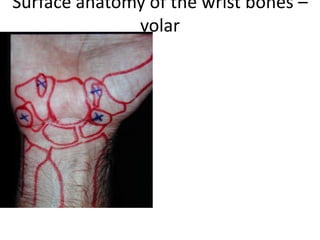

- Naming the bones, joints, tendons, nerves and skin landmarks of the hand and wrist.